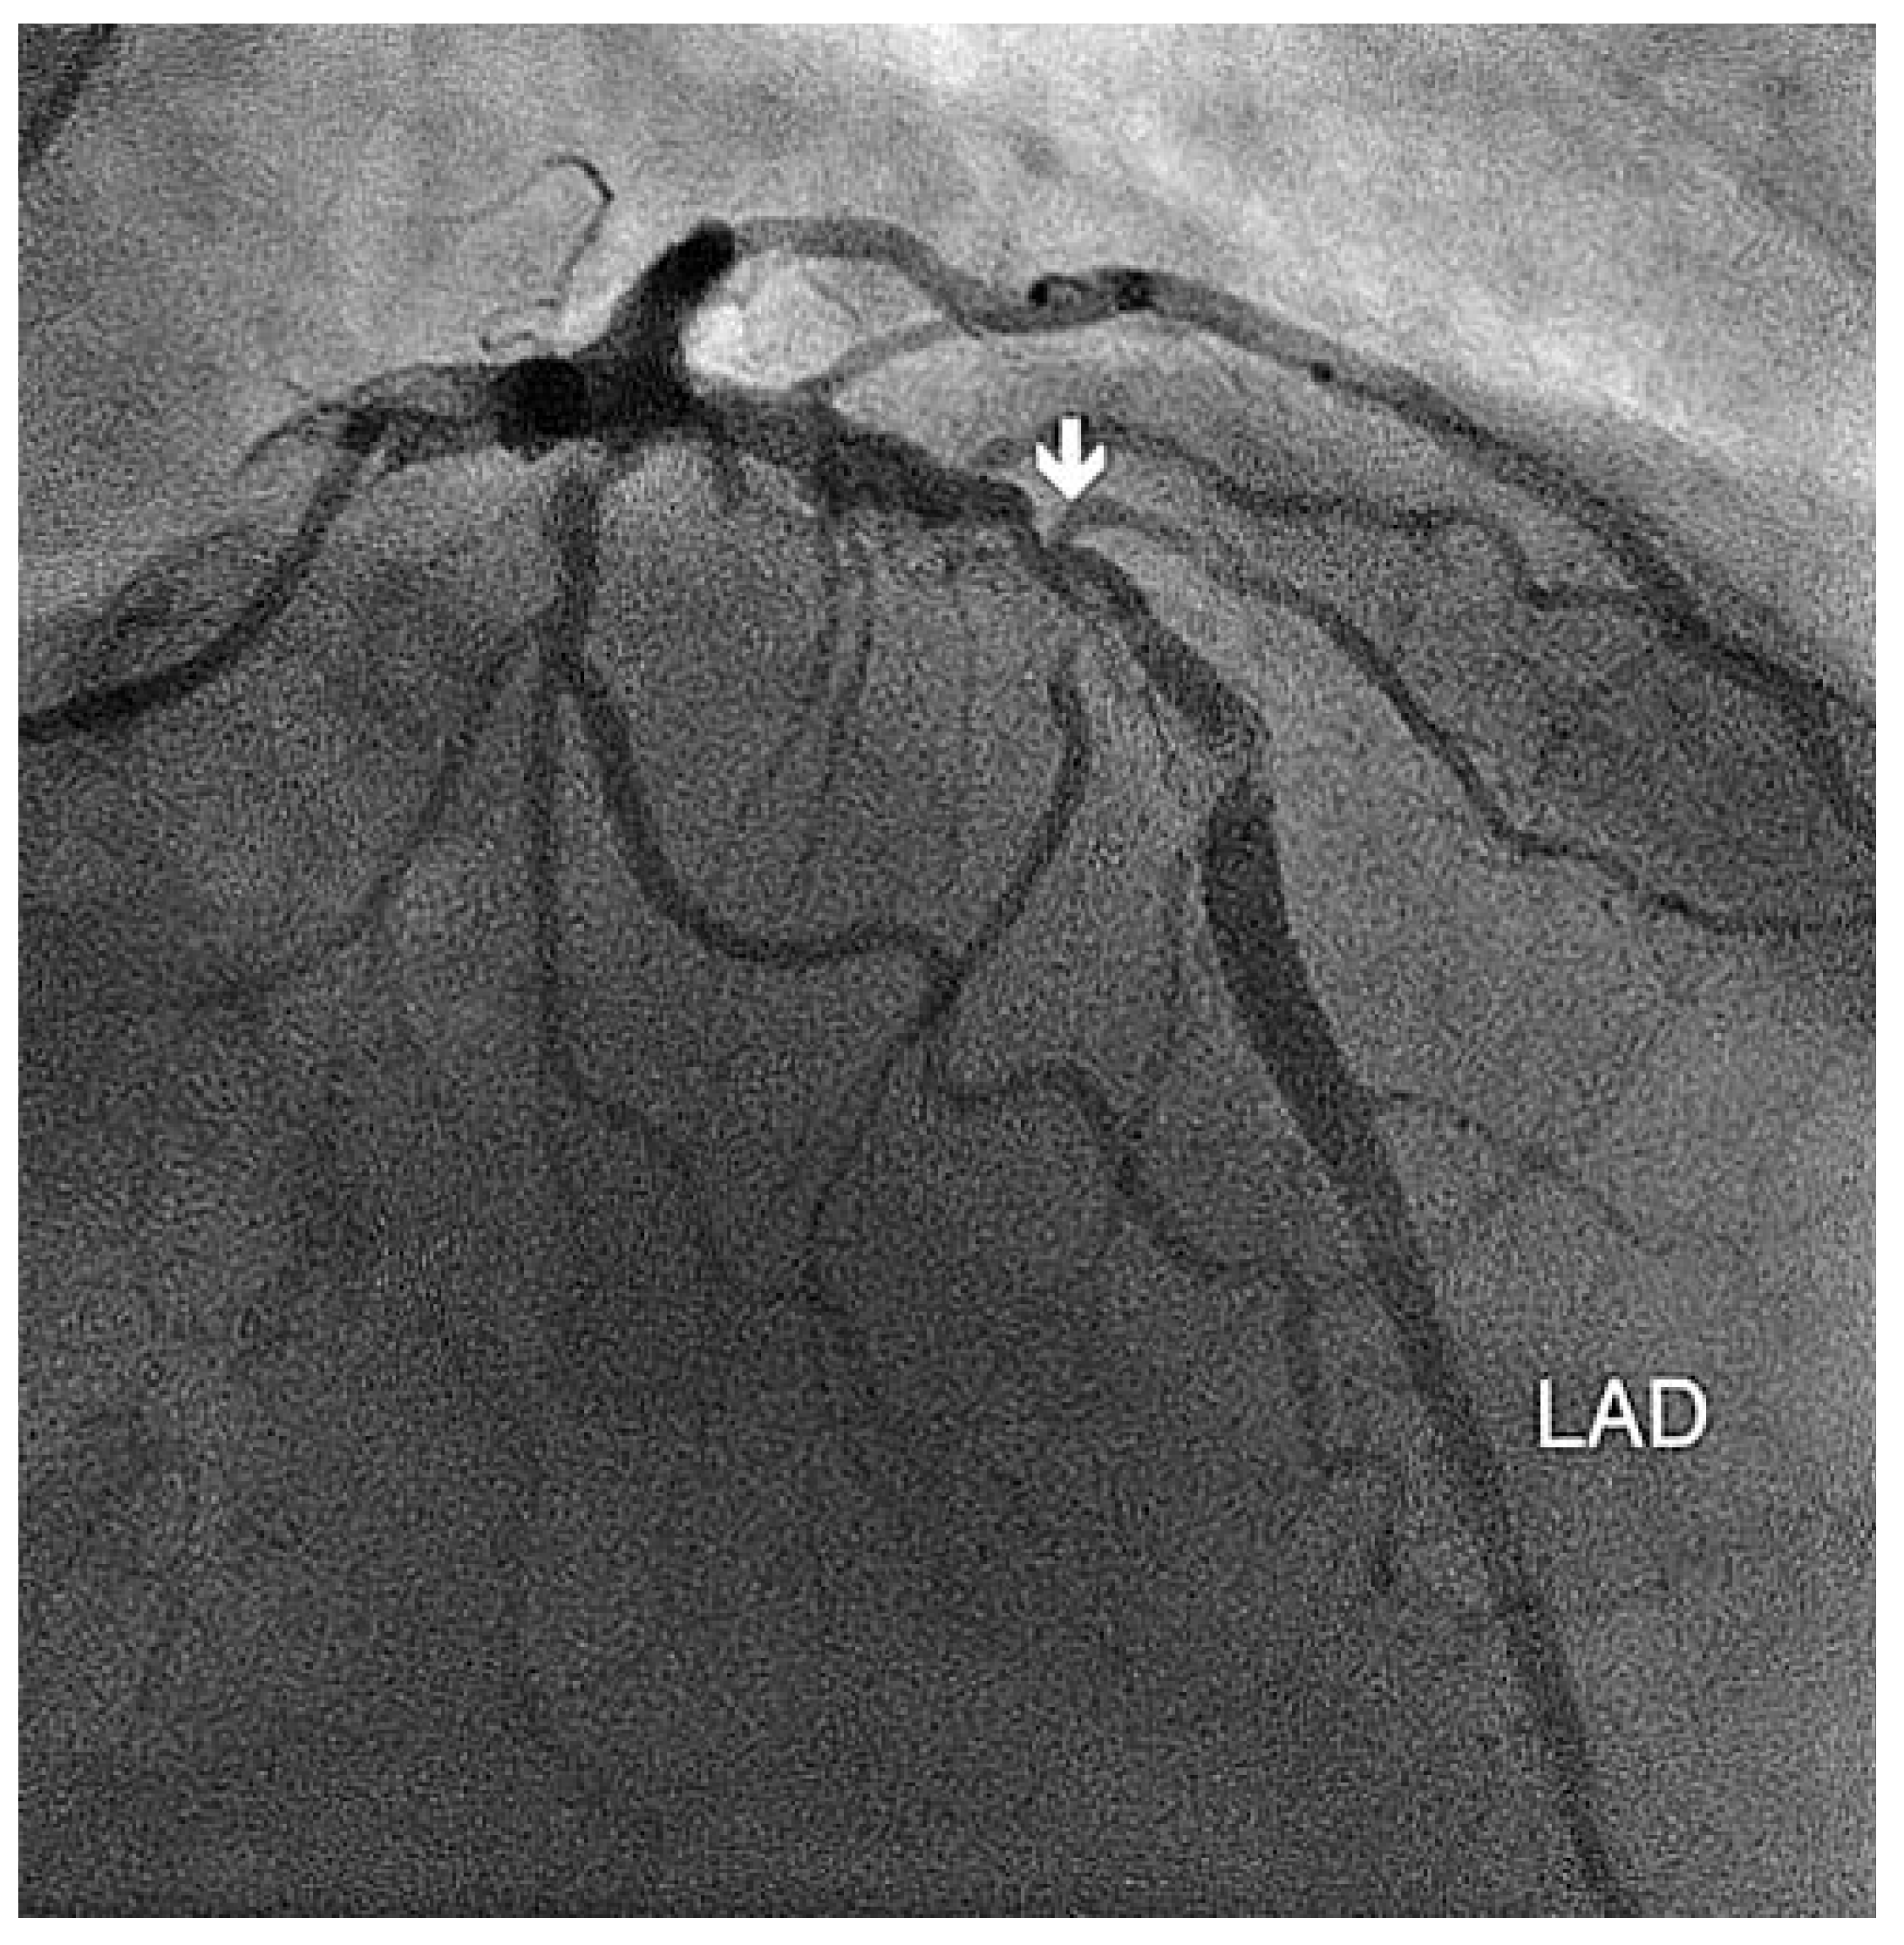

Koronarstenose Und Transthorakale Farbdopplerechokardiographie

Fallbeschreibung